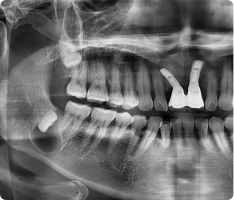

함치성 낭종은 나지 않은 치아(주로 사랑니, 송곳니) 주위에 생기는 물주머니(낭종)입니다.

치아가 잇몸 속에서 올라오지 못하고 머물면서 그 주위에 액체가 고여 발생합니다.

- 흔히 사랑니나 매복된 송곳니에서 발견됩니다.

- 크기가 커지면 주변 뼈를 흡수하거나, 옆 치아 뿌리를 밀어 손상시킬 수 있습니다.

- 대부분 통증이 없어 정기적인 X-ray 검사에서 우연히 발견되는 경우가 많습니다.

- 국소마취 후 잇몸을 열어 낭종과 함께 원인 치아를 제거합니다.

- 낭종 벽을 깨끗이 적출하여 재발을 막습니다.

- 병리검사를 통해 정확한 진단을 확인합니다.

- 작은 경우는 간단히 제거가 가능하고, 큰 경우는 단계적으로 치료하기도 합니다.